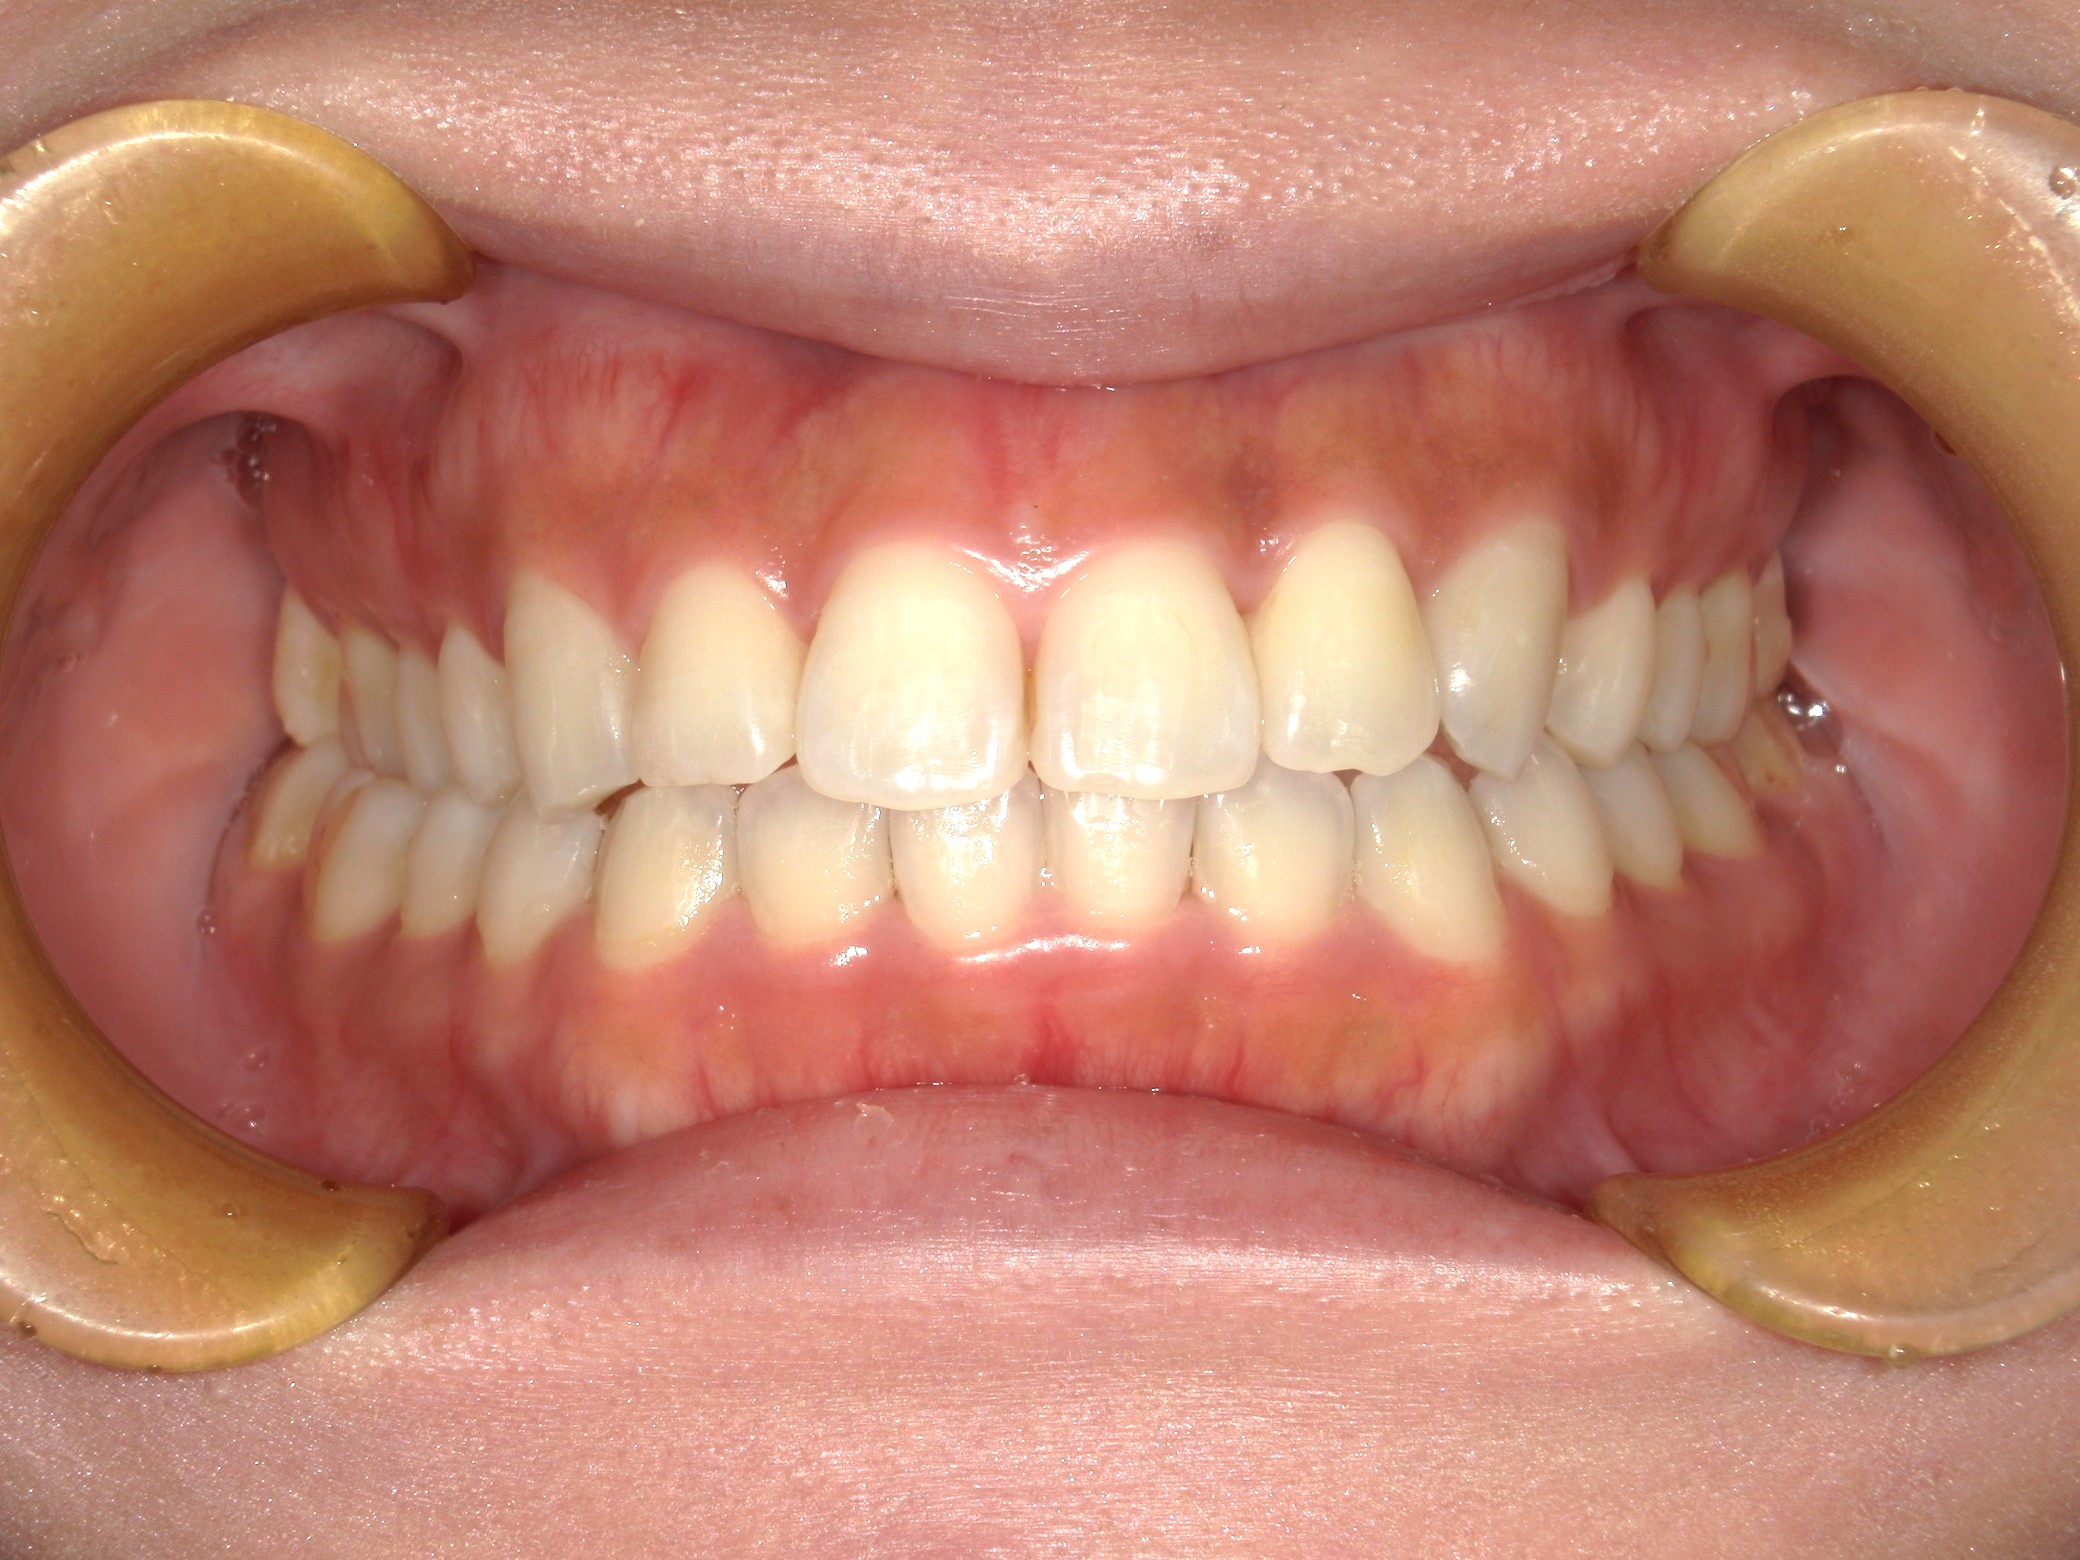

口内正面

治療前

治療後

上顎左右側切歯に約90度の捻転を認め、また咬合不良を認めました。

マウスピース矯正を希望されたため、前歯にIPRを行うことで捻転改善のスペースを作り、非抜歯にて配列することとしました。

90度近い捻転となると、マウスピース矯正単独では改善が難しいため、顎内でのゴムを使用し改善を図ることとしました。

結果的には十分な捻転の改善を達成し、咬合も正しく確立されました。